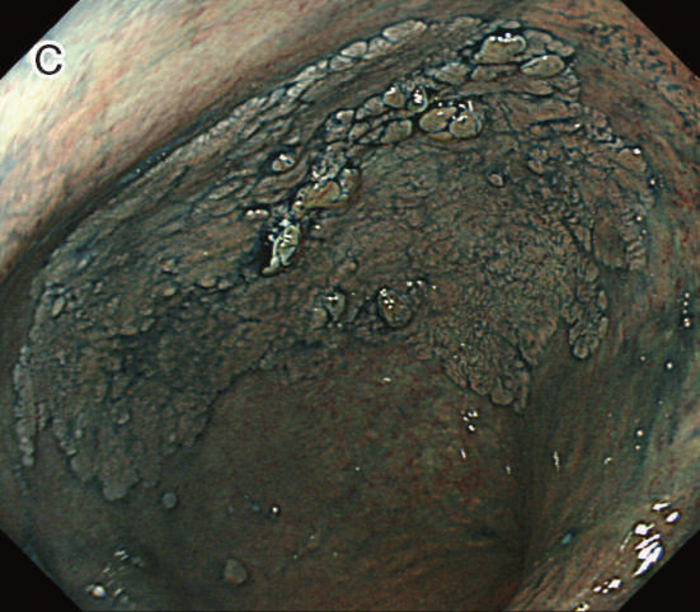

図5 UC関連粘膜下層浸潤癌の内視鏡所見

- 白色光像:直腸(直腸S状部)の発赤調変化。背景粘膜は寛解期にあった。

- 色素内視鏡像:病変辺縁が明瞭となるが,病変肛門側で不明瞭であった。

- NBI拡大像:口径不同,不均一な微小血管と不整な表面構造所見を認めた。

- pit pattern像:小型の類円形,管状pitを認めた。